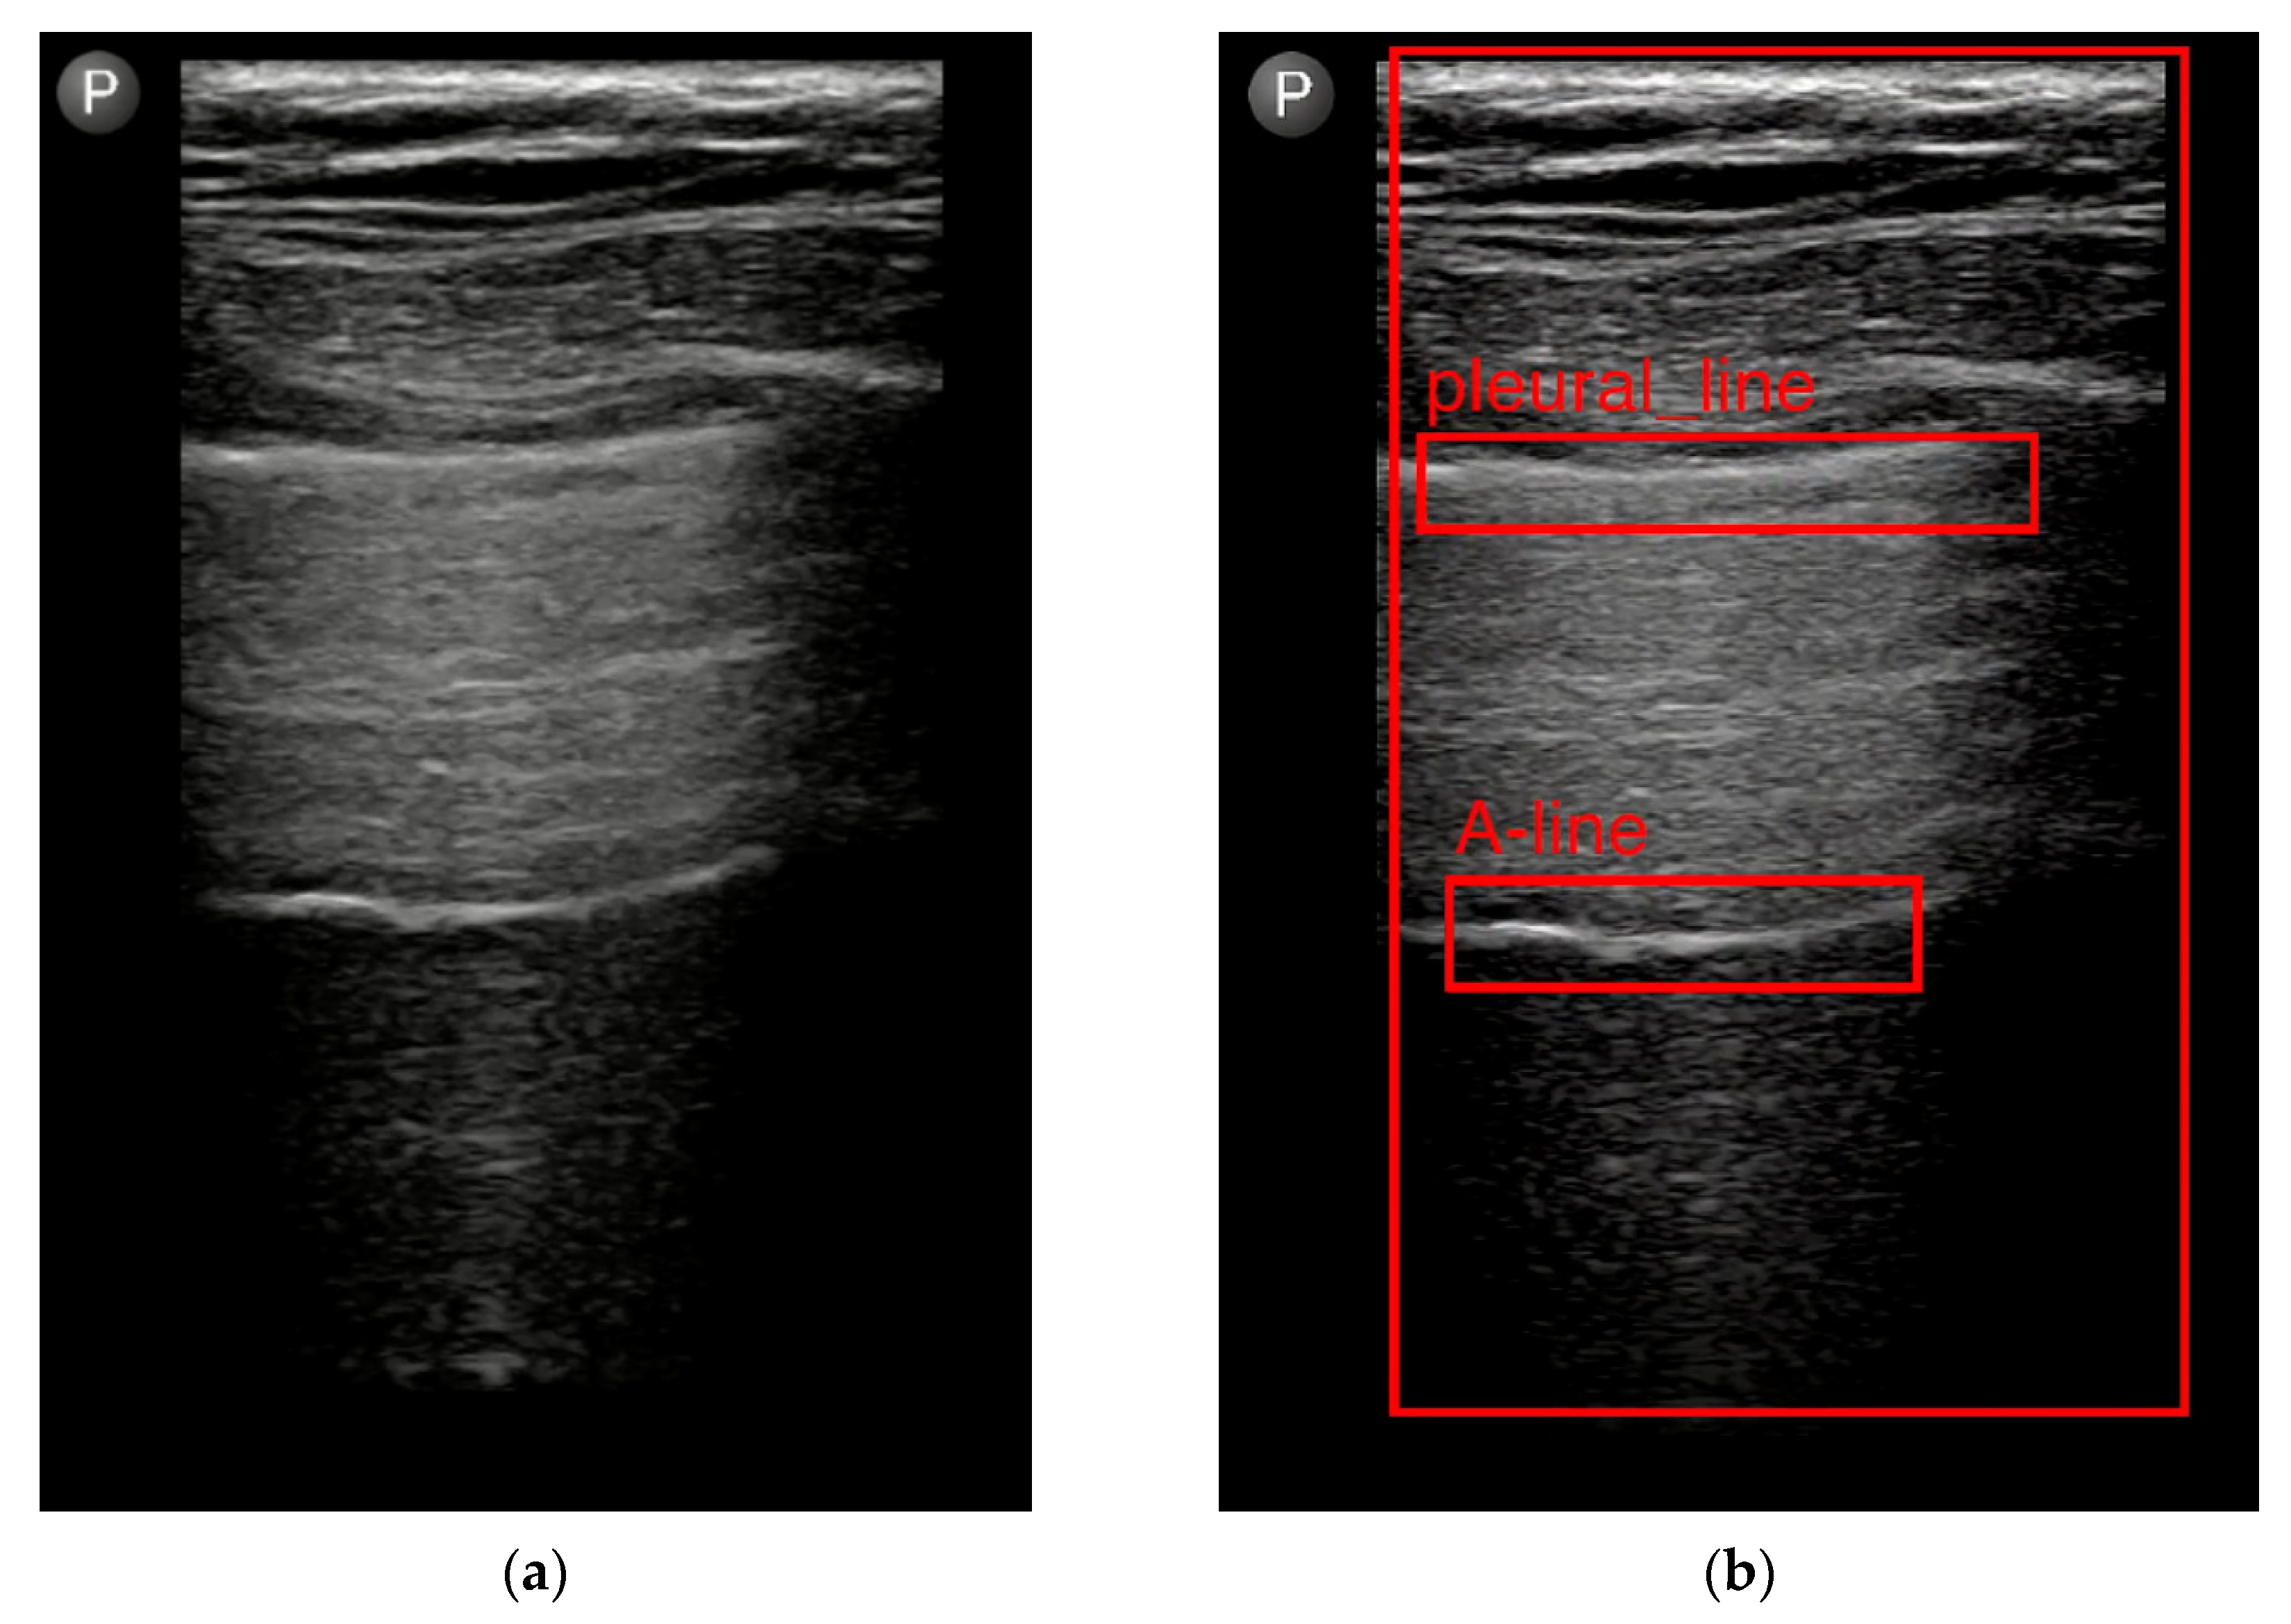

- Hliboký, M.; Magyar, J.; Bundzel, M.; Malík, M.; Števík, M.; Vetešková, Š.; Dzian, A.; Szabóová, M.; Babič, F. Artifact Detection in Lung Ultrasound: An Analytical Approach. Electronics 2023, 12, 1551. [Google Scholar] [CrossRef]